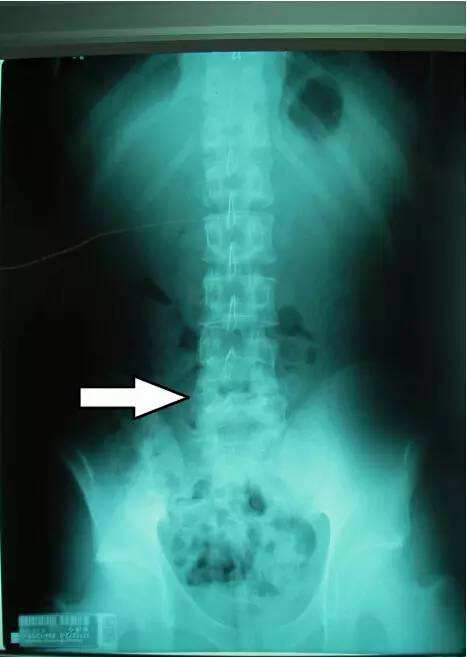

我们总是太过注重工作了,忽视自己的健康,强直性脊柱炎的病情在发病之后,很多患者都会感到严重的疼痛出现,因为这种病情不是那么容易治疗的,长期的药物治疗也有一定的副作用,那么常见的强直性脊柱炎应该怎么办?引起强直性脊柱炎原因有什么?

强直性脊柱炎能治好吗?工作固然重要,但是也不可以忽视自己的健康,强直性脊柱炎病情在不断的影响到患者的身体健康很多患者出现疼痛状况,就会使得工作学习受到严重的影响,对这种病情要尽早的到医院做详细的治疗,特别是物理治疗措施也是非常关键的。